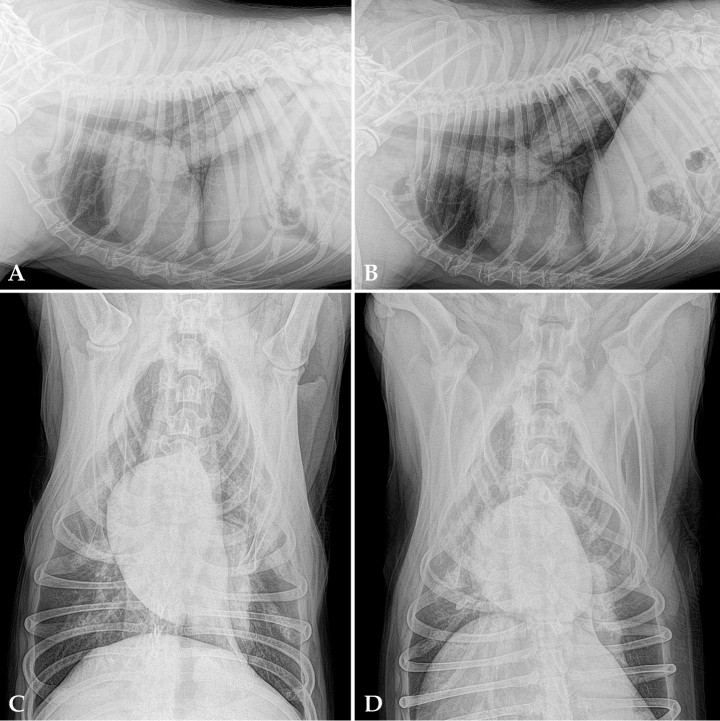

Se realizó un estudio radiográfico de la cavidad torácica, incluyendo cuatro proyecciones: lateral derecha, izquierda, ventrodorsal y dorsoventral (Fig. 1).

<p>Radiografías de tórax en un perro con decaimiento, inapetencia y fatiga de cuatro meses de evolución y episodios de tos no productiva en las últimas tres semanas. (A) Proyección lateral derecha. (B) Proyección lateral izquierda. (C) Proyección ventrodorsal. (D) Proyección dorsoventral.</p>

Radiografías de tórax en un perro con decaimiento, inapetencia y fatiga de cuatro meses de evolución y episodios de tos no productiva en las últimas tres semanas. (A) Proyección lateral derecha. (B) Proyección lateral izquierda. (C) Proyección ventrodorsal. (D) Proyección dorsoventral.

Se observa una masa de opacidad tejido blando, cilíndrica y de márgenes irregulares en el lóbulo caudal izquierdo, extendiéndose desde la carina hacia caudodorsal. El resto de estructuras intratorácicas no muestran alteraciones radiológicas significativas. A nivel extratorácico se evidencia una severa espondilosis, más acusada en T11, T12, T13, L1 (Fig. 2).

<p>Mismas imágenes que la Figura 1. Se observa una masa de opacidad tejido blando cilíndrica de márgenes irregulares en el lóbulo caudal izquierdo, extendiéndose desde la carina hacia caudodorsal (área delimitada en blanco). El área negra señala la espondilosis severa en T11, T12, T13, L1.</p>

Mismas imágenes que la Figura 1. Se observa una masa de opacidad tejido blando cilíndrica de márgenes irregulares en el lóbulo caudal izquierdo, extendiéndose desde la carina hacia caudodorsal (área delimitada en blanco). El área negra señala la espondilosis severa en T11, T12, T13, L1.